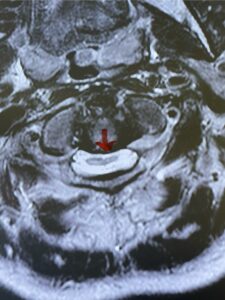

Fig. 4b: Axial T2-weighted cervical MRI demonstrating severe spinal cord compression from atlanto-axial instability (red arrow)

Fig. 6c: Axial cervical CT scan demonstrating a very thin right C2 isthmus (red arrow) compared to left side.